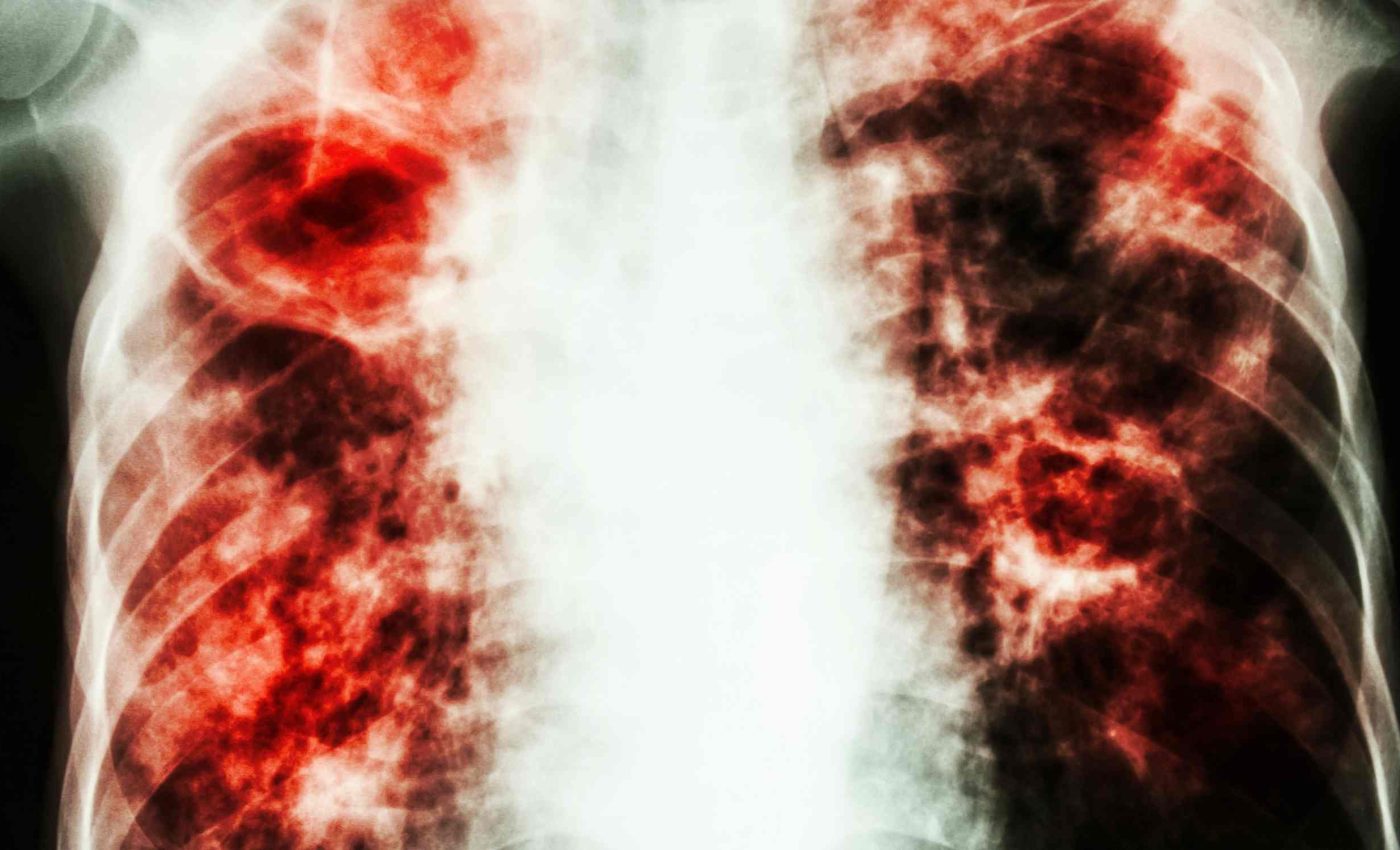

Respiratory Syncytial Virus (RSV) is a common winter virus that targets the airways of young children and older adults. It can cause bronchiolitis and pneumonia that lead to low oxygen levels and breathing support.

The global burden is heavy. A 2022 analysis estimated about 33 million RSV lower respiratory infections in children under 5 in 2019, with millions of hospital stays worldwide.